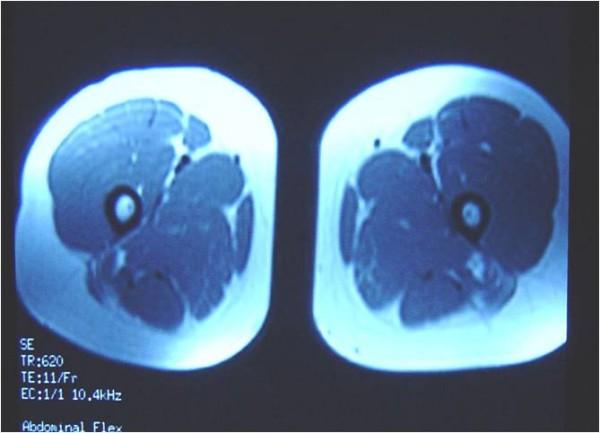

We report the case of a 21-year-old Greek Caucasian female rowing athlete who was injured on both thighs. She complained of pain and inability to walk. Physical examination revealed tenderness over the thighs and restriction of knee movement. The result of a roentgenogram was normal, and there was no evidence of fracture or patella displacement. Magnetic resonance imaging revealed haematoma formation in both the rectus femoris muscles. The diameters of the left and right haematomas within the muscles were 6 cm and 5 cm, respectively. Therapeutic approaches included compression bandages, ice application, rest, elevation, and administration of muscle relaxant drugs. Active stretching and isometric exercises were performed after three days. The patient was able to walk using crutches two days after the initiation of treatment. On the seventh day, she had regained her full ability to walk without crutches. Non-steroidal anti-inflammatory drugs were administered on the fifth day and continued for one week. Six weeks later, she had pain-free function and the result of magnetic resonance imaging was normal. She was able to resume her training programme and two weeks later, she returned to her previous sport activities and competitions.

我们报告一例21岁的希腊白人女性赛艇运动员双侧大腿受伤的病例。她主诉疼痛且无法行走。体格检查发现大腿压痛及膝关节活动受限。X线检查结果正常,无骨折或髌骨移位迹象。磁共振成像显示双侧股直肌均有血肿形成。肌肉内左侧和右侧血肿直径分别为6厘米和5厘米。治疗方法包括加压包扎、冰敷、休息、抬高患肢以及给予肌肉松弛药物。三天后进行主动拉伸和等长运动。治疗开始两天后患者能够借助拐杖行走。第七天,她已完全恢复不用拐杖行走的能力。第五天给予非甾体类抗炎药并持续一周。六周后,她功能正常且无疼痛,磁共振成像结果也正常。她能够恢复训练计划,两周后,她重返之前的体育活动和比赛。